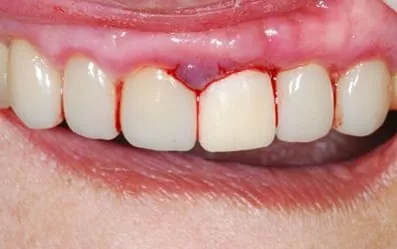

治療前:左上大門牙撞斷

治療前:左上門牙疼痛、動搖,牙齦周圍有一圈黑黑的發炎。

採取無創傷性拔牙,看到牙根確實已斷裂